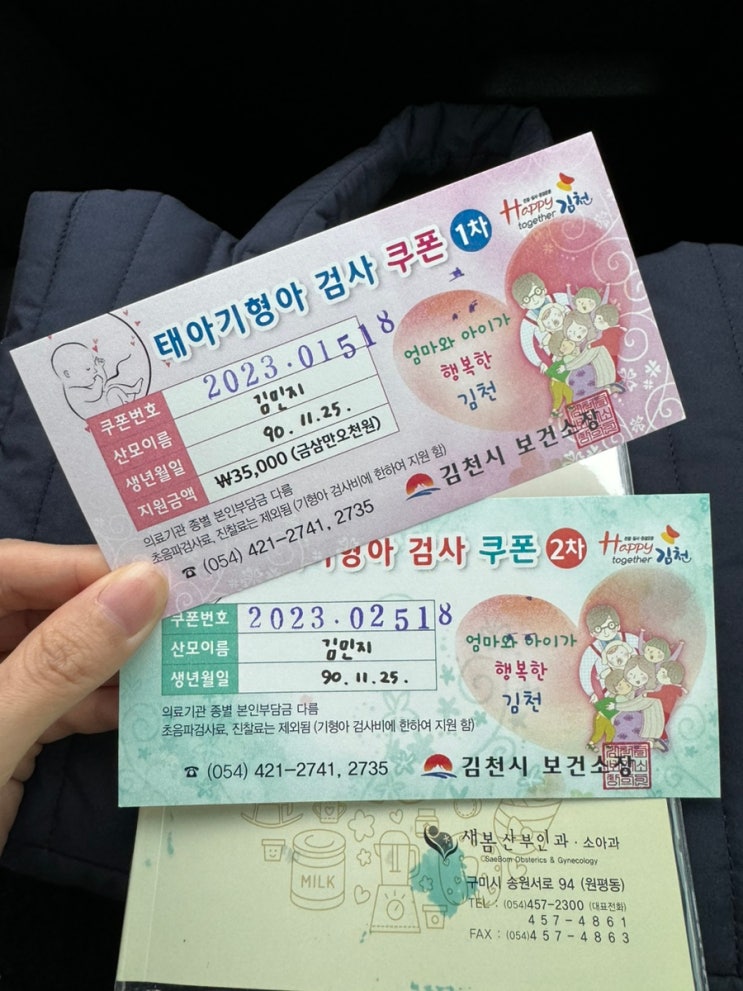

[엄마 깅밍징 기록] 20주차 : 태아성장보고서 / 초음파 보는 법 / 자궁경부길이

#20주차 안녕 반짜가✨ 한달 왜이렇게 길어ㅠ_ㅠ 잘있는지 넘나 궁금했다구 아가는 내가 생각한거보다 훨씬...